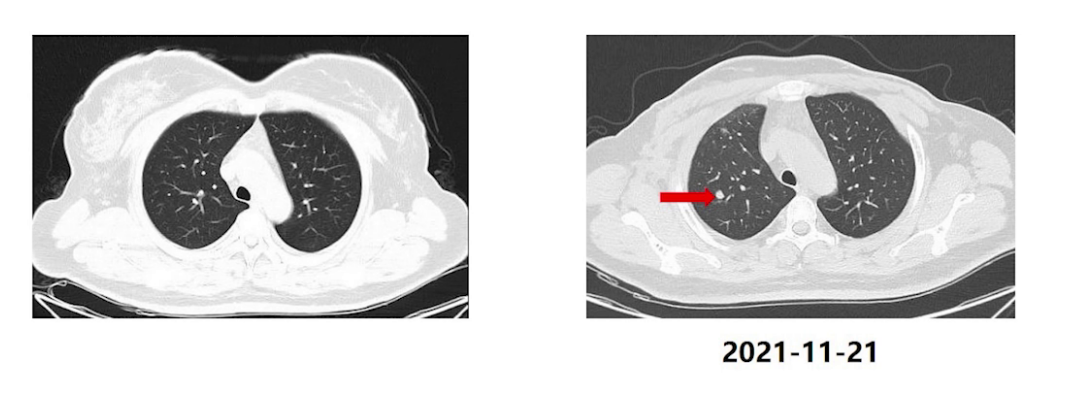

2021年11月21日查胸腹部CT,提示两肺多发实性结节,最大位于右肺上叶,直径约9mm,较前新发转移可能大,头颅MRI及骨扫描未见明显异常。

MDT讨论:影像科考虑肺转移性结节可能大,不排除肺原发肿瘤可能,但病灶小,穿刺难度大;胸外科认为可以切除活检,明确病变性质;肿瘤科认为可以先行全身抗肿瘤治疗,控制稳定以后可以考虑行局部的治疗。